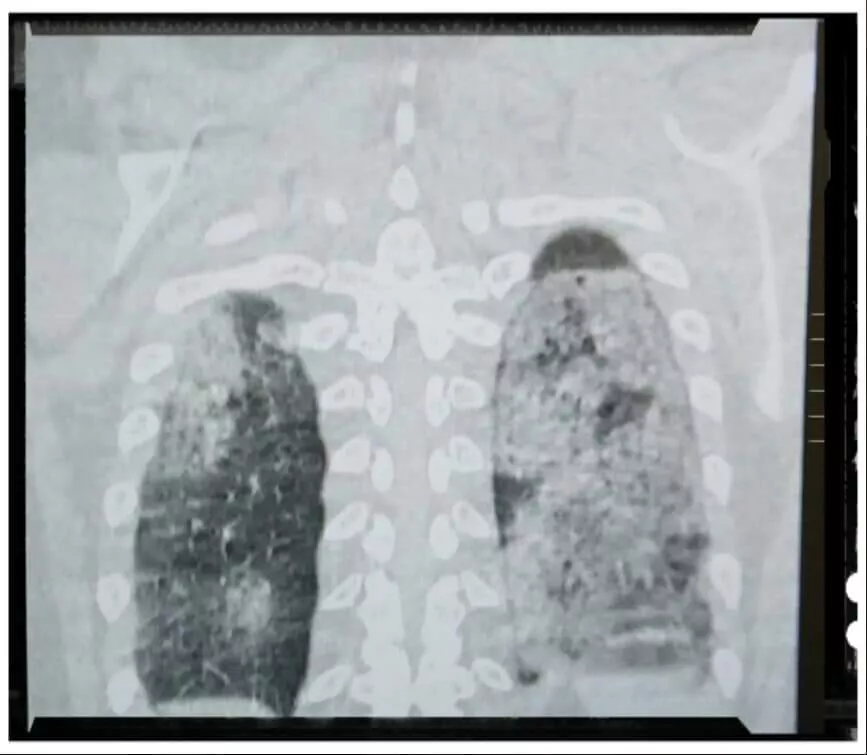

"Danas u Sarajevu 430 hospitaliziranih na Covid odjeljenjima. Ovo je CT pluća jednog od njih, mlad čovjek, nepušač, do sada zdrav. Za one koji ne znaju, zdrav je crni dio pluća.

Doktori, neznalice, peta kolona, diktatori itd. posegnuli su za slamku spasa i ordinirali lijek koji je pacijent kupio. Oporavlja se.

Lijek je skup i ne može se nabaviti na teret zdravstvenog osiguranja.

I svi ostali hospitalizirani bolesnici imaju upalu pluća. Nadati se da će što manje njih imati ovako tešku.